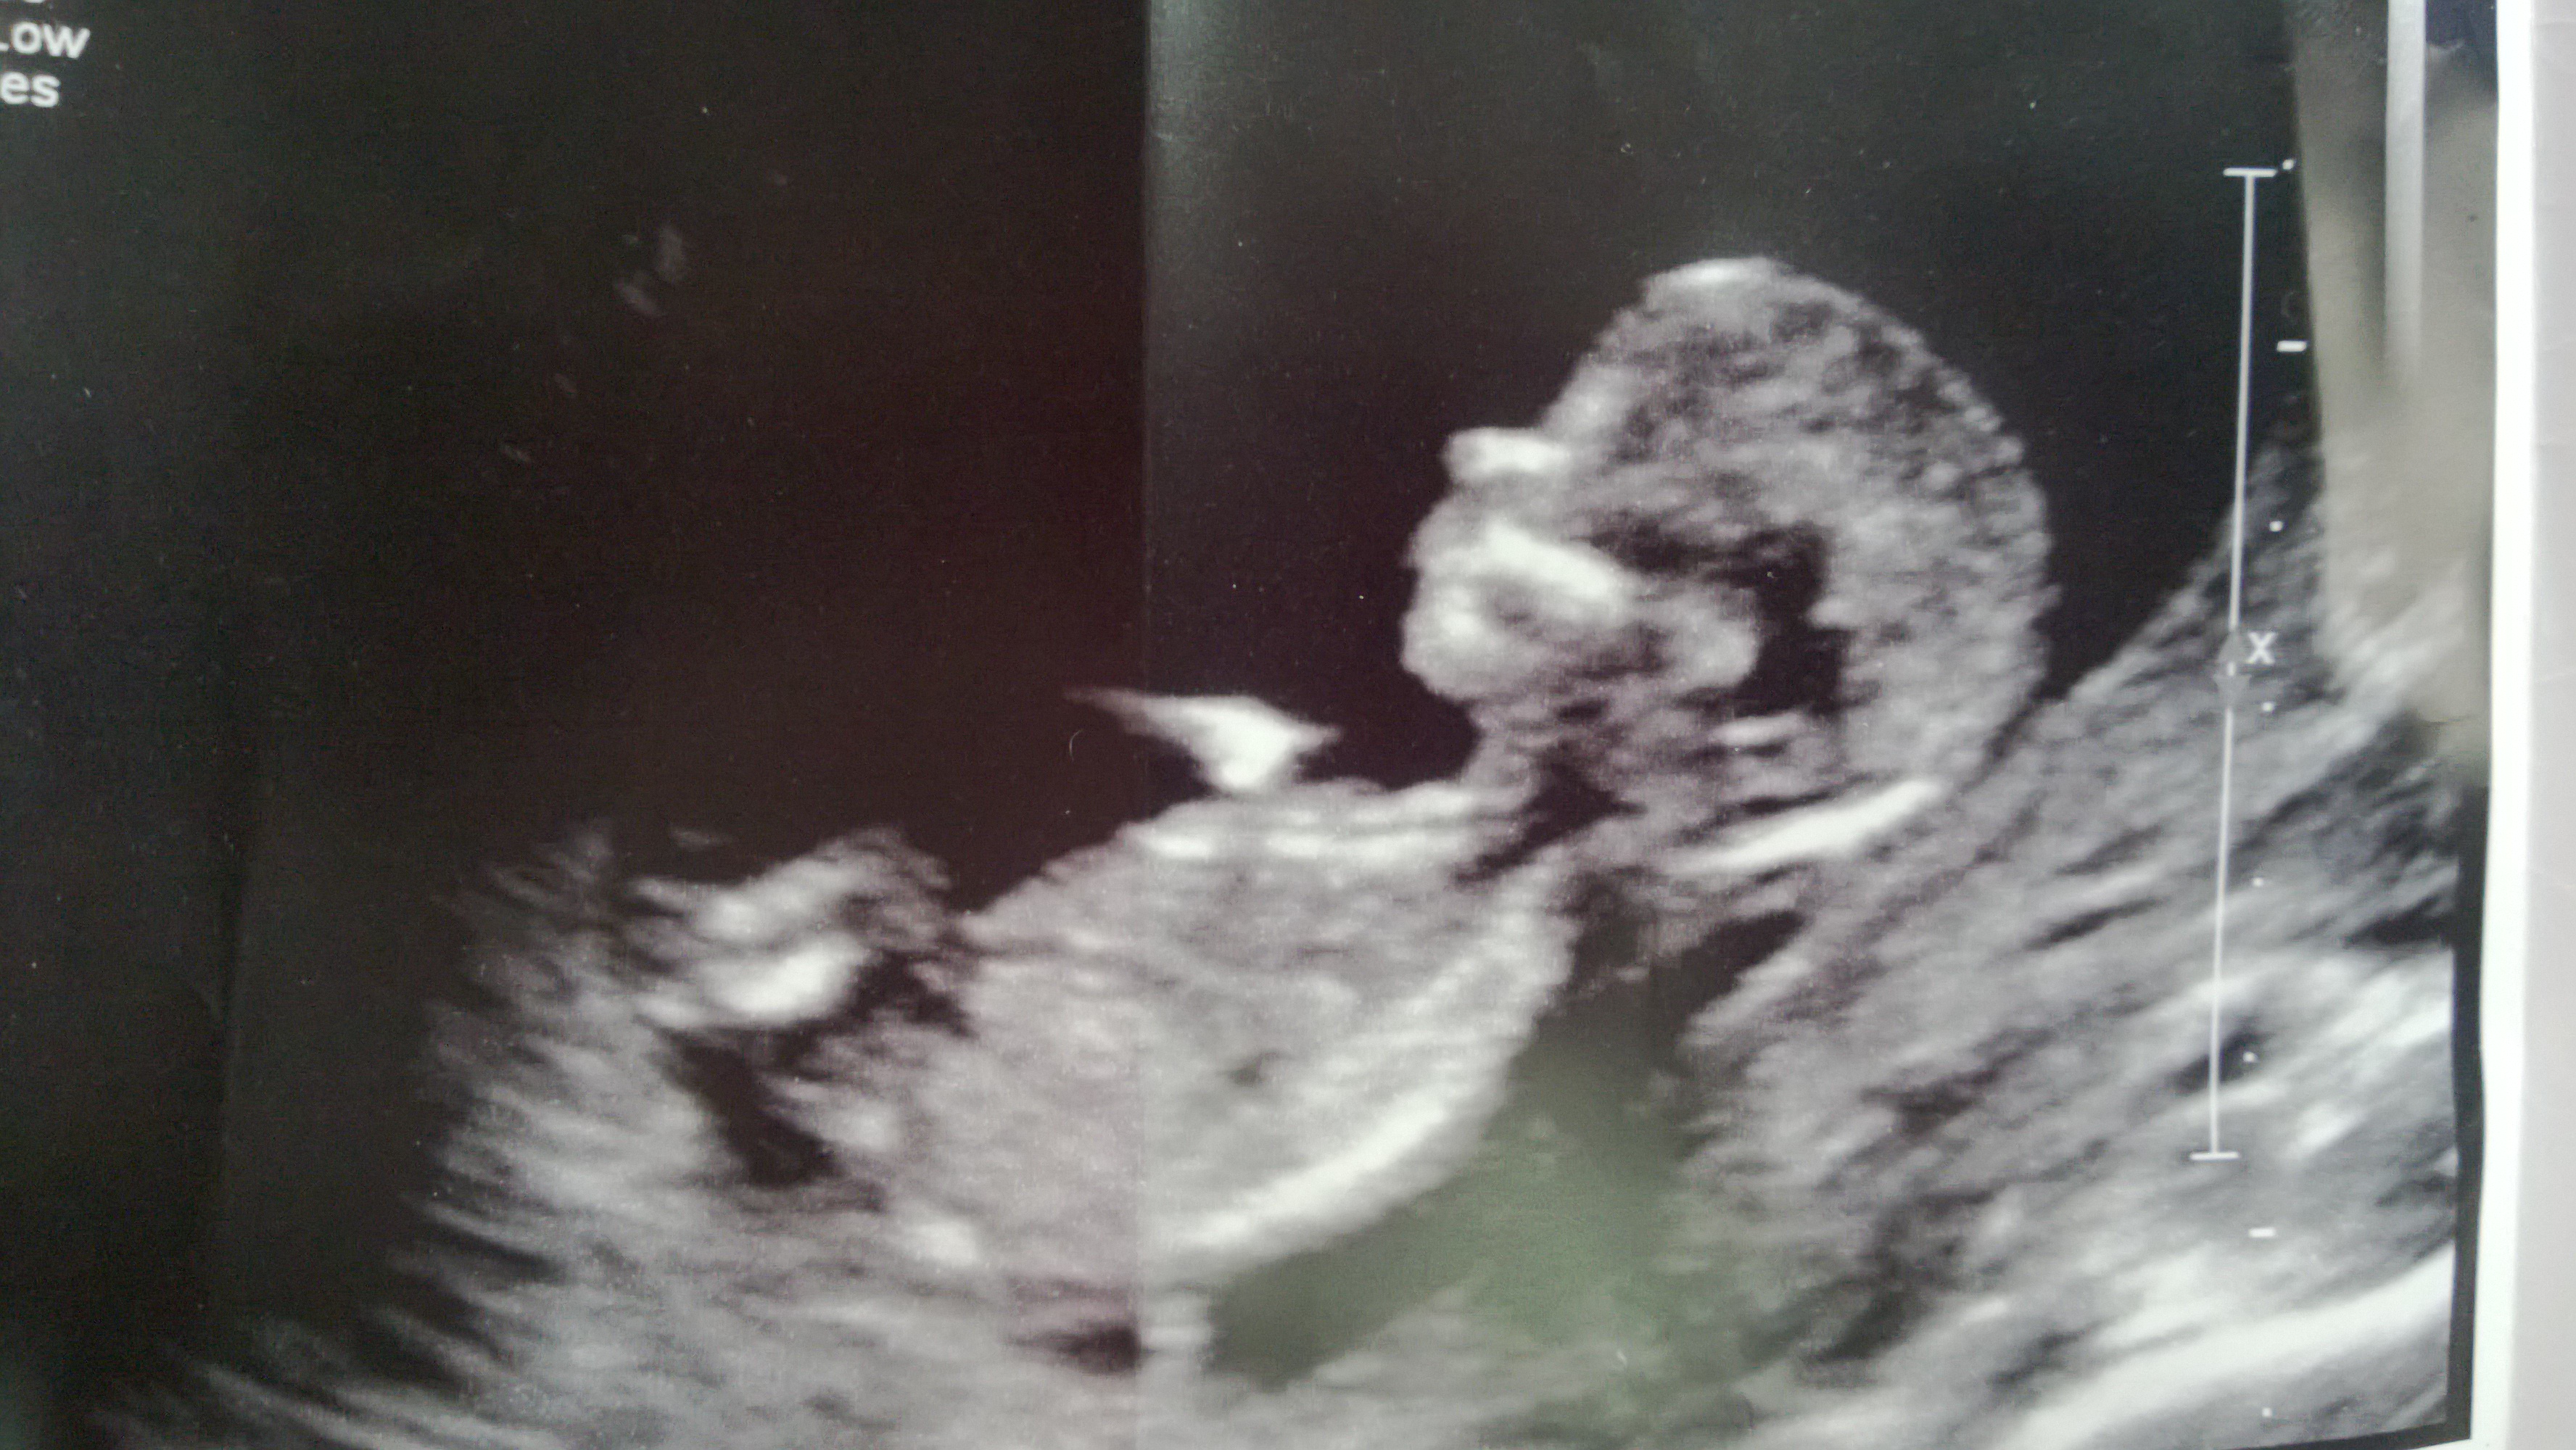

This is a 13w1d NT scan. Experts, please guess the gender of the baby. Thank you!

Went for a private gender u/s at 17 weeks, confirmed GIRL!! Saw the 3 lines and everything. Still in shock, very excited since I wanted a girl. I guess there is still hope for those who want a girl, but nubs look like boy.